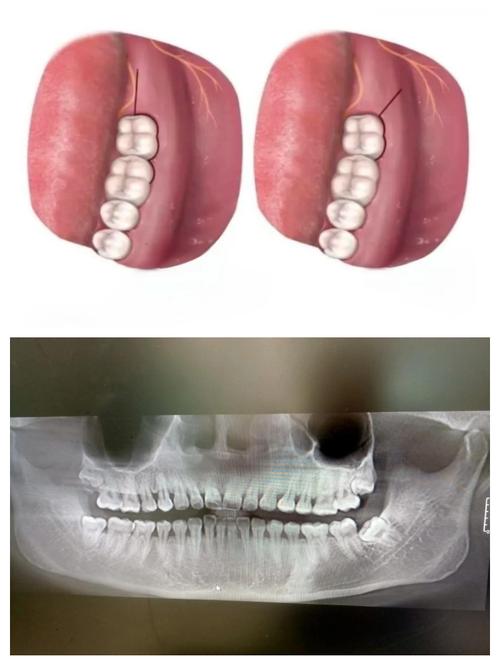

冠向复位瓣术(Coronally Advanced Flap, CAF)

冠向复位瓣术是将患牙牙龈向牙冠方向移动,覆盖暴露的牙根,常与结缔组织移植术联合使用(CAF+CTG),以增强覆盖效果和牙龈稳定性。

- 切口设计:在退缩牙龈的根方做水平切口,两侧做垂直松弛切口,形成矩形牙龈瓣。

- 翻瓣与根面处理:翻开全厚瓣,彻底清创根面,平整根面,必要时用EDTA处理。

- 结缔组织移植(CAF+CTG):若行CAF+CTG,则在受区植入结缔组织瓣,增加牙龈厚度。

- 冠向复位与缝合:将牙龈瓣向冠位复位,覆盖移植组织和根面,用悬吊缝合或水平褥式缝合固定,确保无张力。

- 术后处理:术后使用塞治剂,1周拆线,4周内避免术区受力。